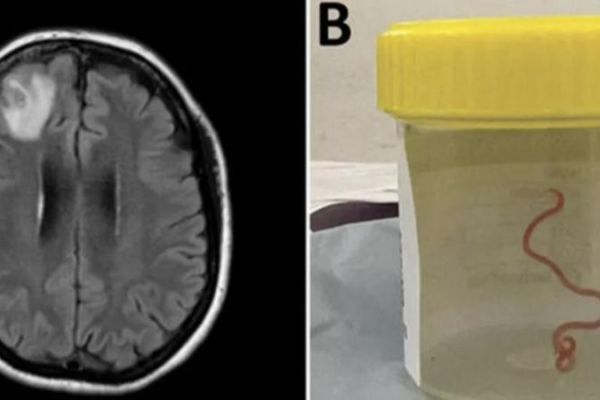

Qadının beynindən canlı qurd çıxarılıb